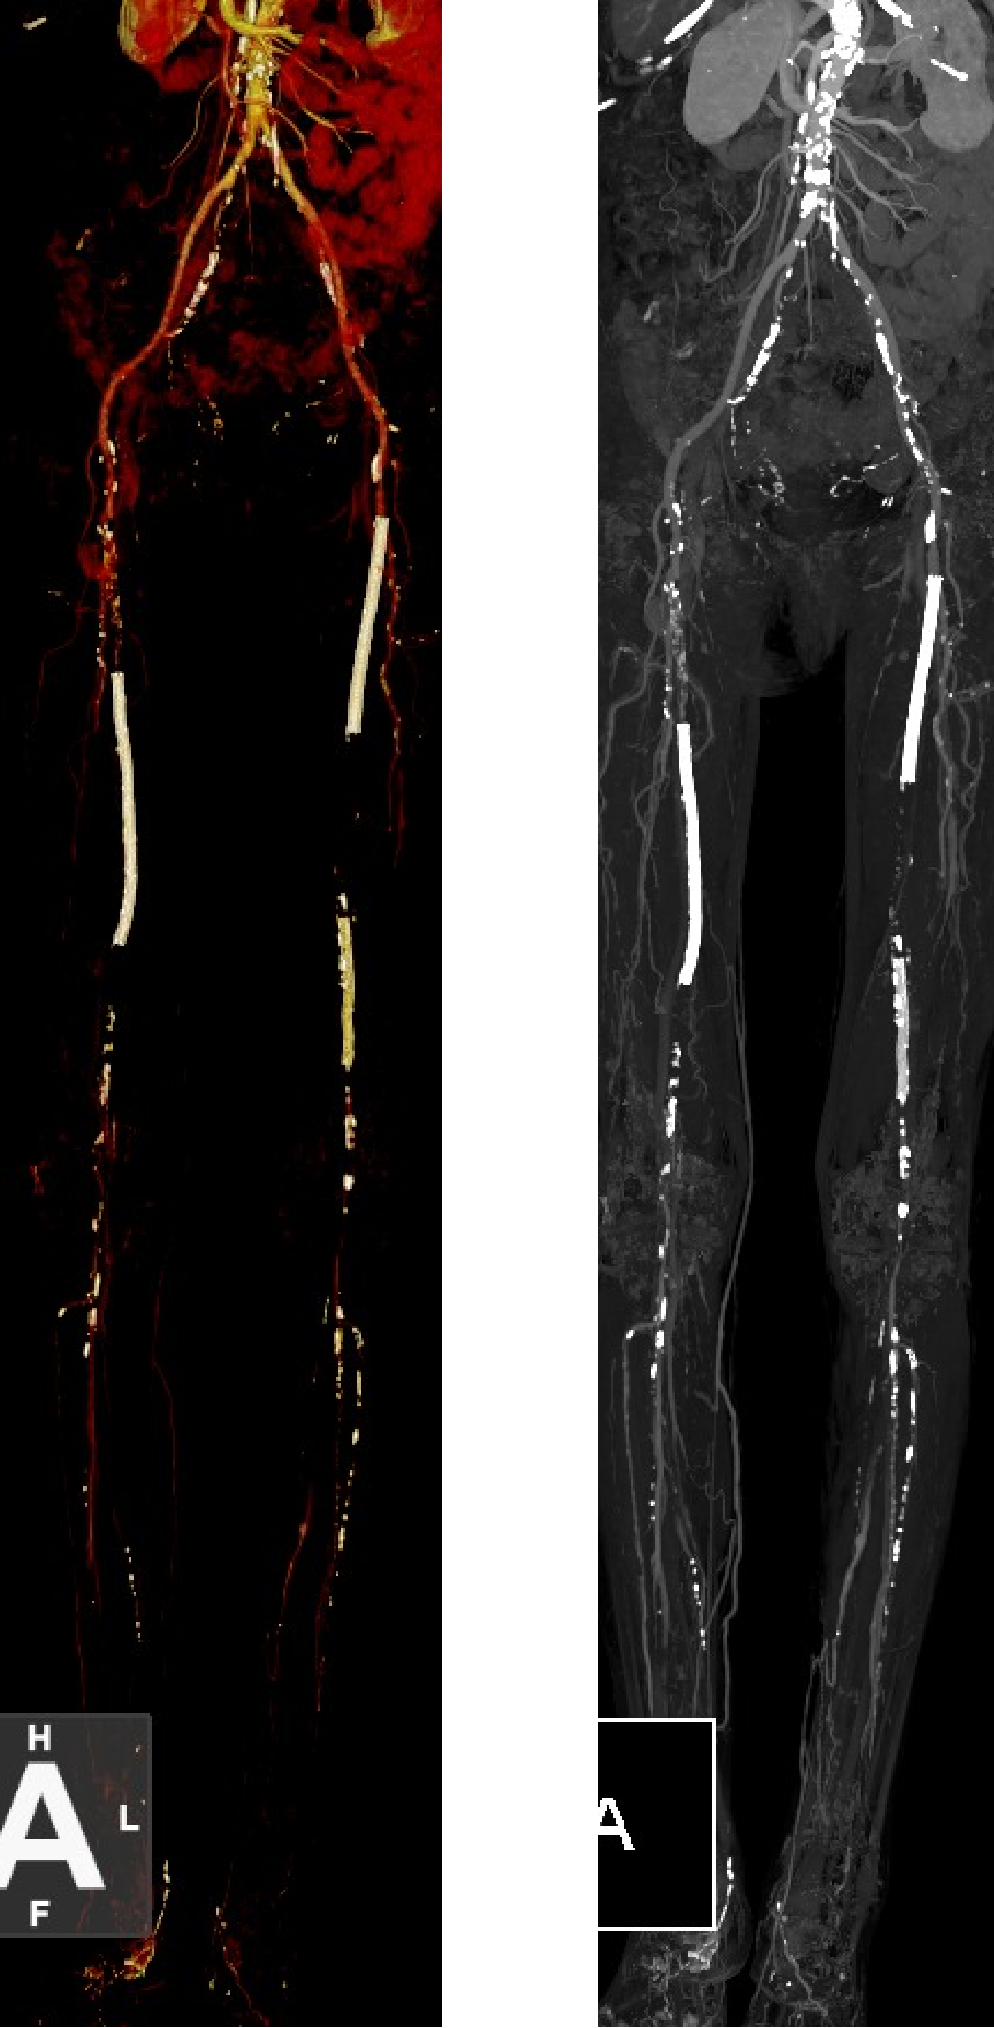

★ 病例基本情况

84岁女性患者,因"右足背、拇趾溃疡半年,支架植入术后4年余"就诊。患者4年前因下肢缺血行支架植入术,近期症状复发加重。

图:术前CT

★ 术前评估

血管造影显示股腘动脉长段支架内再狭窄,伴有严重钙化。

★ 术后结果

血管造影显示管腔明显改善,血流恢复良好

图:术后造影